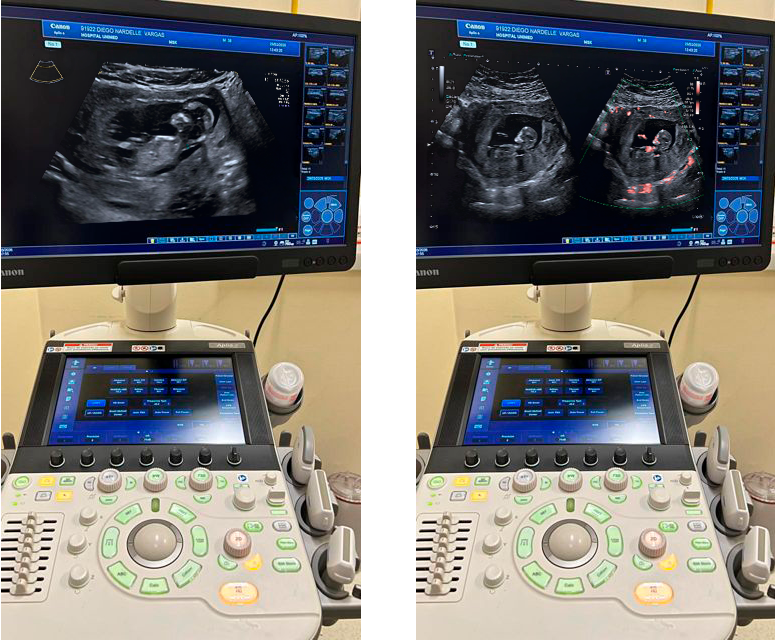

O novo equipamento oferece mais precisão, agilidade e conforto para pacientes e médicos, sendo um dos aparelhos de ultrassom de mais alta tecnologia.

Cuidar da saúde é, também, investir em recursos que tornem o diagnóstico cada vez mais seguro, rápido e confortável. Pensando nisso, a Unimed Anhanguera acaba de incorporar ao seu parque tecnológico o ultrassom Aplio a Smart, um equipamento moderno e de alta performance que reforça o compromisso da cooperativa com a qualidade assistencial.

Com tecnologia de ponta e imagens em alta definição, esse ultrassom permite que os médicos visualizem estruturas com mais detalhes e nitidez, o que contribui para diagnósticos mais precisos e decisões clínicas mais assertivas.

Os recursos avançados do equipamento também oferecem melhor avaliação de fluxos sanguíneos e tecidos, apoiando o acompanhamento de diferentes condições de saúde.

Além da qualidade de imagem, o novo ultrassom foi desenvolvido para trazer mais agilidade ao dia a dia. Sua interface intuitiva e ferramentas de automação ajudam a otimizar o tempo de exame, facilitando o trabalho da equipe e proporcionando uma experiência mais confortável para o paciente, com menos tempo em sala e um fluxo de atendimento mais organizado.

O novo equipamento é versátil e pode ser utilizado em diversos tipos de exames, como avaliações abdominais, vasculares, musculoesqueléticas, ginecológicas, obstétricas e cardiológicas, de acordo com a indicação médica. Isso amplia a capacidade da Unimed Anhanguera de oferecer diagnósticos por imagem completos, com alto padrão de qualidade.

“Investir em tecnologia é investir em cuidado. Com o Aplio a Smart, damos mais um passo para oferecer diagnósticos cada vez mais precisos, mantendo o foco no acolhimento e na experiência dos nossos pacientes”, destaca o dr. José Carlos Anselmo de Andrade.